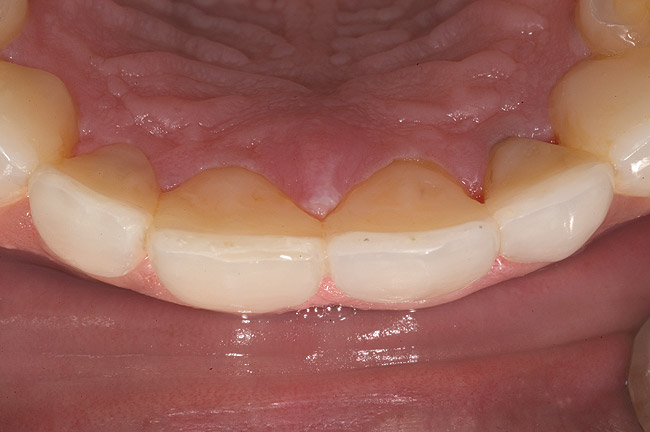

Figure 18  1:1 view of restored palatal surfaces with nanofilled resin.

Figure 18

White enamel shade was placed on the putty index and carried to the palatal surface of No. 9. This layer was spread uniformly and thinned out and spread along the entire width of the tooth (Figure 11). After curing this layer, A2 dentin was layered to simulate the lobular pattern seen in dentin of the natural teeth (Figure 12). After curing, a layer of transparent resin was placed in the incisal areas between the dentinal lobes. The final layer of A2 enamel was built and shaped to full contour (Figure 13). A similar build-up was done for all the remaining anterior teeth. The bite in MIP was adjusted such that there was uniform contact on all anterior teeth. The anterior guidance was harmonized to maintain uniformity in the contact of the incisors during protrusion and the canines and incisors during lateral excursions. Finishing and polishing was done per protocol (Figure 14 through Figure 18).13

A simple, additive option using direct resin as presented in this case for management of localized palatal wear using the modified Dahl’s principle allowed the patient to retain his residual anterior tooth structure. Nano­filled formulations of light-cured resin were used because they have better strength, wear resistance, and optical properties as compared to hybrid composites and have shown good survival rates in high-stress situations. It needs to be emphasized that these newer formulations of composite resins, when used in such cases of significant function—even with excellent adjustment and guidance—will have surface loss at greater rates than metal or ceramic surfaces. However, in young patients, additive resin techniques allow the clinician to buy time and save crucial tooth structure so that future definitive restorative options may be exercised.